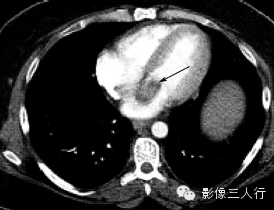

| 心房黏液瘤(图1) | 纤维瘤(图2) | 脂肪瘤(图3) | 横纹肌肉瘤(图4) | |

好发

年龄 |

成人 | 婴幼儿 | 成人 | 儿童或年轻人 |

部位 |

多起源于房间隔,以窄基底与其相连,并向心腔内生长 | 心室心肌内,常见于左室游离壁或室间隔 | 多原发于心外膜,在心房、心室无差异 | 各房室及间隔心肌壁均可发生,常累及一个以上心腔,可侵犯心包和大血管 |

病灶

形态 |

圆形或椭圆形,多呈浅分叶状,有蒂与心房间隔相连,肿瘤位置可随心动周期而变化,有时脱入左室 | 卵圆形或分叶状,常有薄层假薄膜,边界清楚 | 椭圆形或分叶状,边界清楚 | 形态不规则,边界不清,可见坏死、出血 |

CT

密度 |

稍低密度 | 密度稍低于心肌 | 脂肪密度 | 不均匀软组织密度 |

强化

特点 |

不均匀强化 | 强化程度较正常心肌弱 | 无强化 | 一般均匀强化,坏死后内部不强化 |